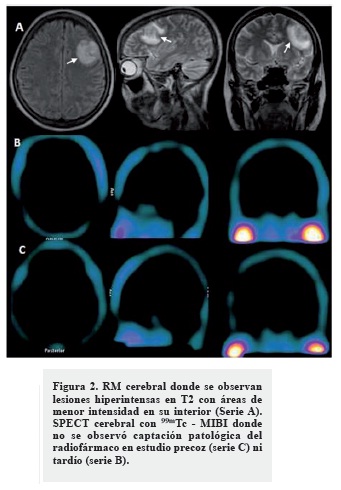

Se realizó una RM cerebral donde se observaron lesiones ligeramente hipointensas en T1 e hiperintensas en T2 con áreas de menor intensidad en su interior (frontal izquierda, occipital derecha y parietal posterior derecha), siendo la mayor frontal izquierda (23 x 21 mm), que no desplazaban las estructuras de la línea media ni producían herniaciones (Figuras 2 y 3, serie A). Las características imagenológicas de estas lesiones tampoco fueron concluyentes para un diagnóstico etiológico de las mismas.

Decidimos realizar una SPECT cerebral con 99mTc - MIBI donde no se observó captación patológica del radiofármaco en el estudio precoz el ni tardío (Figuras 2, serie B y C). Ante la negatividad de este estudio, diagnosticamos que las lesiones evidenciadas en TC y RM de cráneo correspondían a abscesos cerebrales. La paciente fue tratada con antimicrobianos de amplio espectro y en estudio evolutivo a los 20 días -RM cerebral-, se observó una gran mejoría de las lesiones encefálicas (Figura 3).